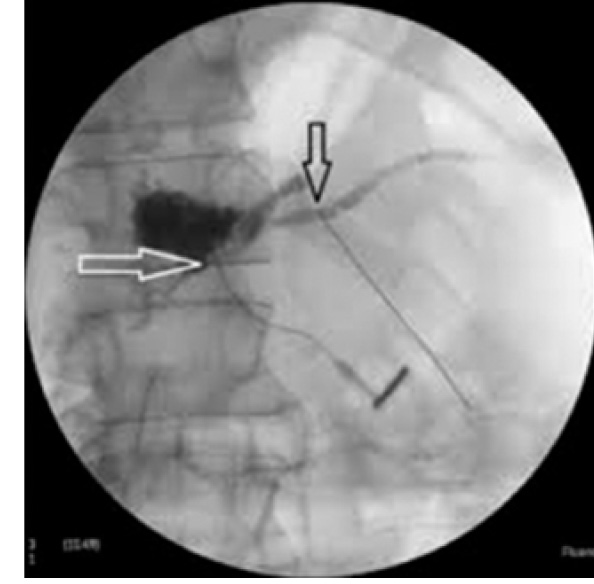

Наличие временного каркасного дренажа позволило подтвердить несостоятельность ПЕА рентгеноконтрастной фистулографией (рис. 6).

Рис. 6. Панкреатическая фистулография. Стрелками обозначены панкреатический проток и зона несостоятельности анастомоза

На основании критериев Международной группы по изучению панкреатических фистул несостоятельность ПЕА анастомоза считали доказанной [7].